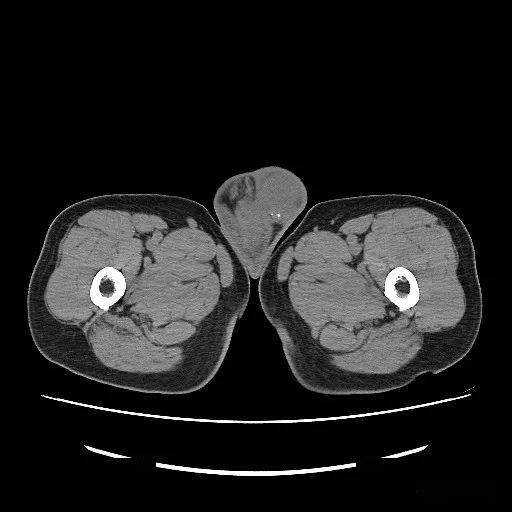

【读片】男性,62岁,三十年前右侧腹股沟肿块,近一月来明显加剧!